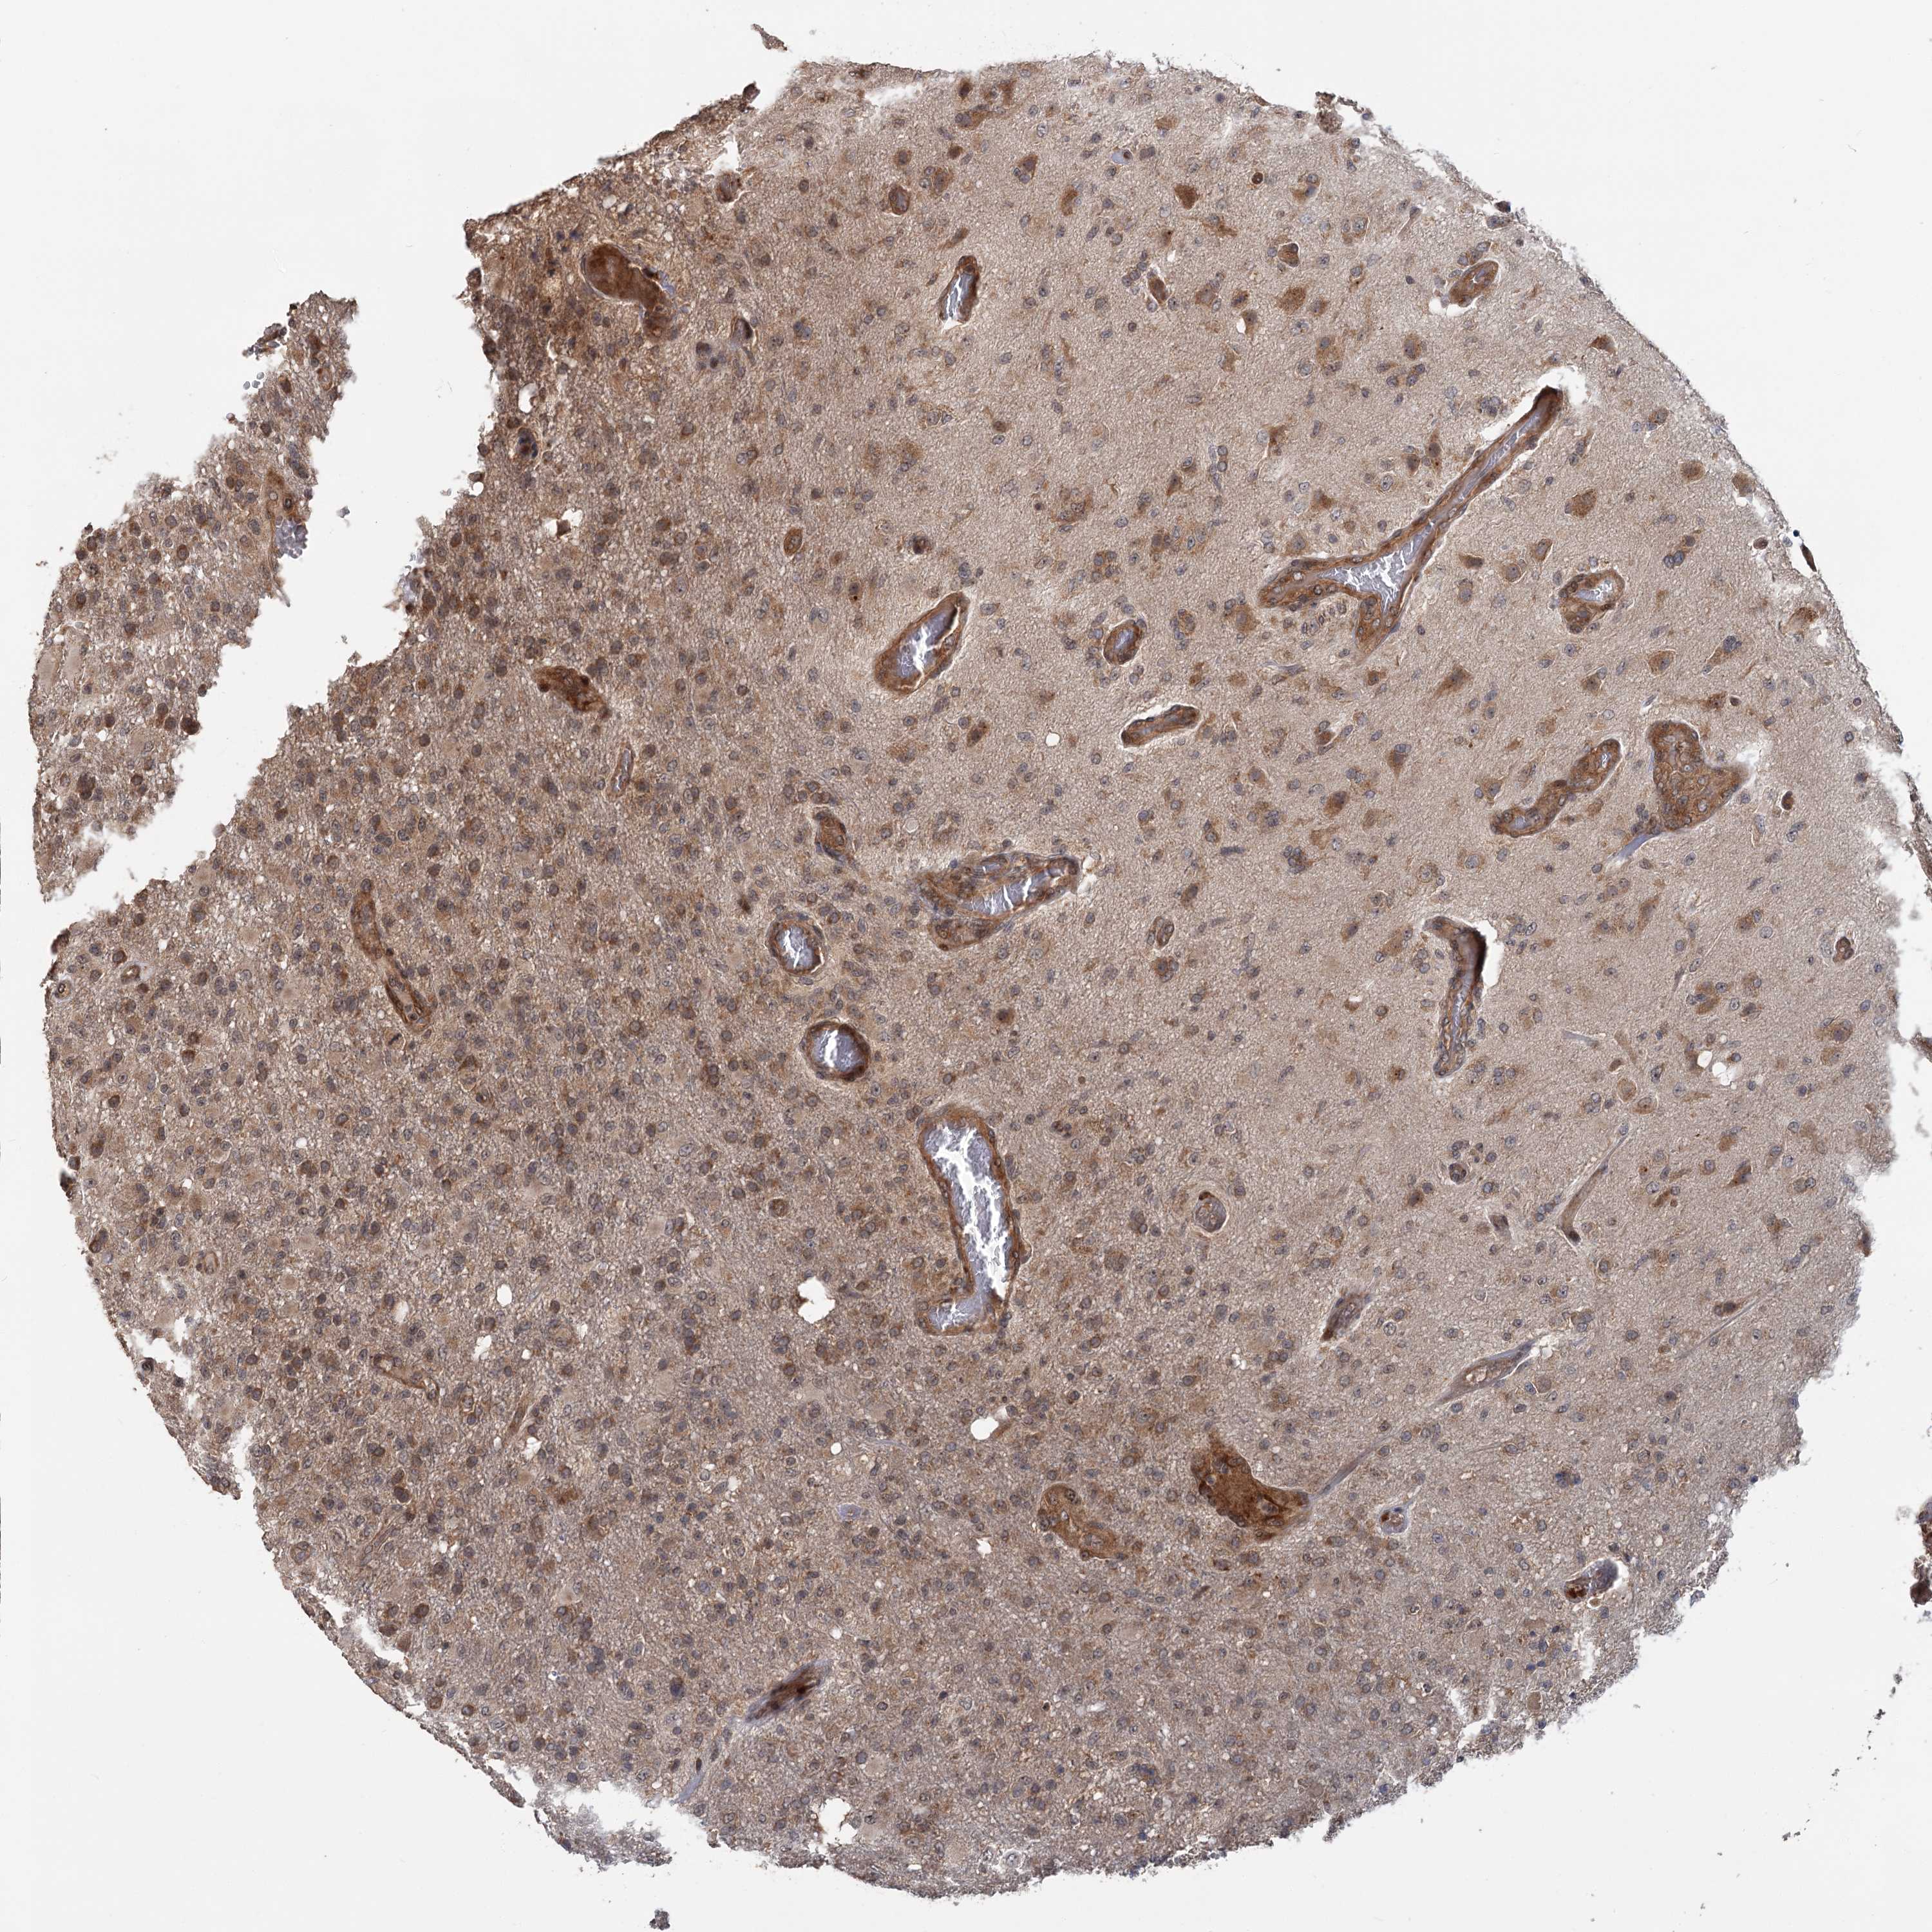

GLIOMA - Protein expressioni

A mouse-over function shows sample information and annotation data. Click on an image to view it in a full screen mode. Samples can be filtered based on level of antibody staining by selecting one or several of the following categories: high, medium, low and not detected. The assay and annotation is described here.

Note that samples used for immunohistochemistry by the Human Protein Atlas do not correspond to samples in the TCGA dataset.

Antibody stainingi

Antibody staining in the annotated cell types in the current human tissue is reported as not detected, low, medium, or high, based on conventional immunohistochemistry profiling in selected tissues. This score is based on the combination of the staining intensity and fraction of stained cells.

Each image is clickable and will lead to virtual microscopy that enables deeper exploration of all samples and also displays staining intensity scores, fraction scores and subcellular localization as well as patient and tissue information for each sample.

Antibody HPA038497

Antibody HPA038498

Staining

High

Medium

Low

Not detected

Intensity

Strong

Moderate

Weak

Negative

Quantity

>75%

75%-25%

<25%

None

Location

Nuclear

Cytoplasmic/membranous

Cytoplasmic/membranous,nuclear

Glioma, malignant, High grade

Glioma, malignant, Low grade